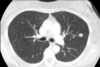

* ¿Qué estudio es? * ¿Qué patrón ves? | Descríbelo:

- TC - **Reticular** "red/telaraña" | Polígono con punto (vaso) en el centro